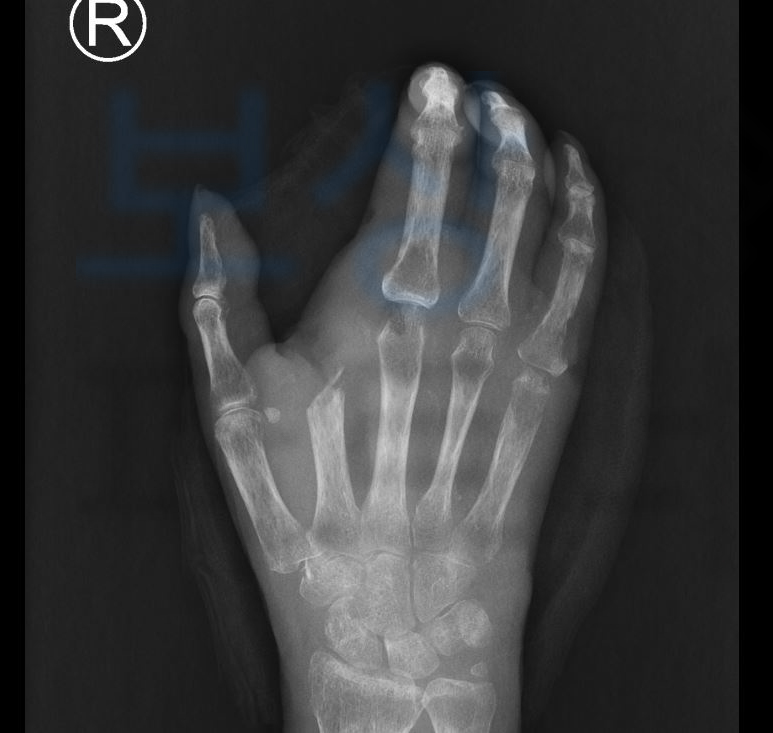

박@@님은 휴대폰을 잡고 넘어져 손가락의 뼈까지 골절되는 깊은 상처를 입고 말았습니다. 하지만 당시 겪었던 사고를 대수롭지 않게 여겼고 핀 고정술 후 고객님은 자연스레 손가락이 회복될거라고 생각하셨는데요

그런데.. 점차 나아지지 않고 점점 부어오르고 심해져가는 열감에 병원을 다시 내원해보니 손가락의 골수염 진단을 받게 되었습니다.

손가락 골수염의 진행을 막기 위해 2수지, 3수지까지 절단술을 감행하는 안타까운 사례였죠. 많은 분들이 개인적으로 처리하실 때 약관상의 내용을 보시고

후유장해 진단을 진행하였고 그 결과 의뢰인은 무려 각 손가락의 장해 뿐 아니라 손목관절의 운동범위도 제한되는 심한 장해에 해당하였고 총 55%의 지급율에 해당하였습니다.

위 장해진단서를 보시면 손목관절의 심한 장해 20% 각 손가락의 뚜렷한 or 절단 장해 35% 여기서 끝이 아니라 보험금 지급의 적정성을 증명하기 위해 손해사정서 와 증빙자료를 함께 각 보험사에 송부하였는데요,